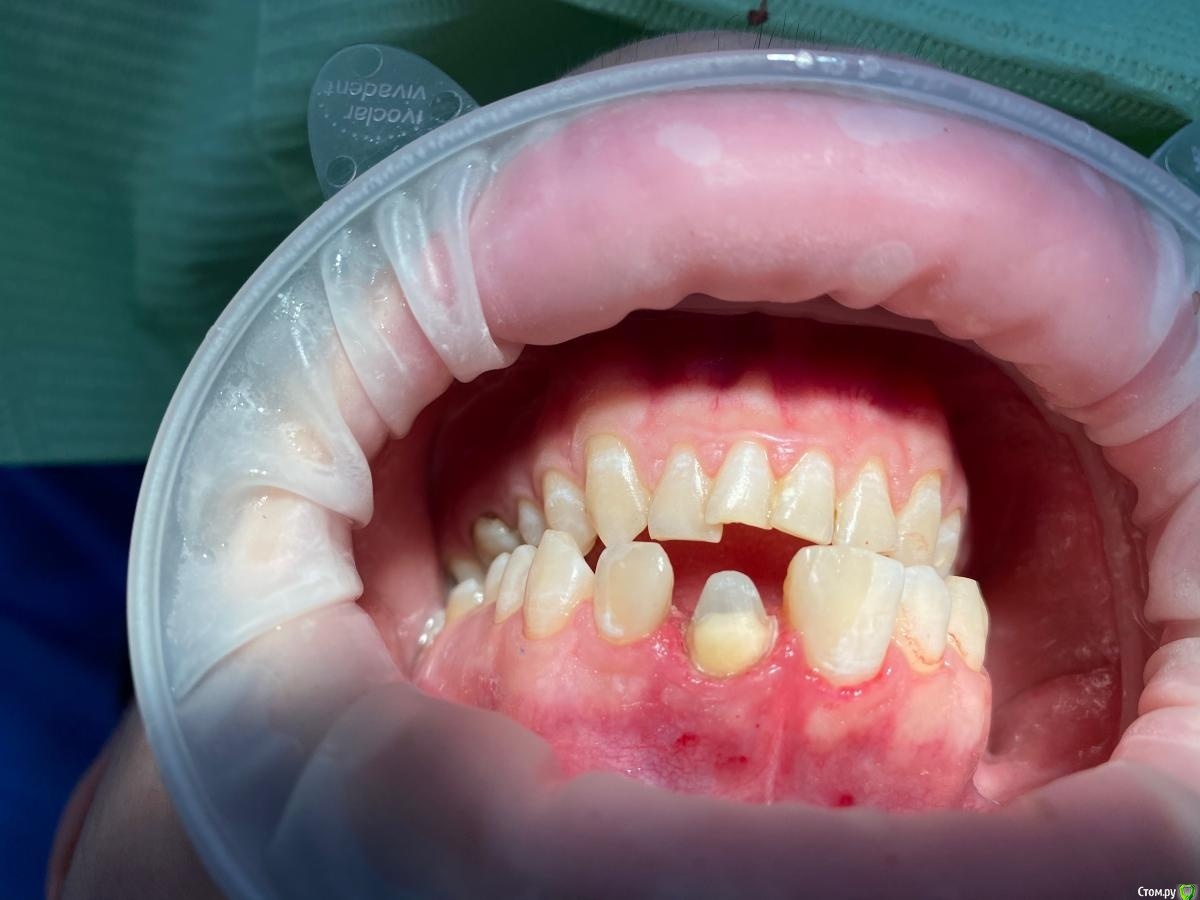

Женька Опубликовано 20 января, 2021 Автор Поделиться Опубликовано 20 января, 2021 Спасибо, коллеги. Я вас понял. Расскажите пожалуйста, как вы учились препарировать с уступом? Сегодня препарировал 2.1... 2 часа я мучал пациента (еще и г**но-времяшку делал). В итого получилось не очень как по мне... Посмотрите фото... это же просто стыд. Конусность запилена, уступ весь кривой-косой. Пересмотрел кучку видео по препу. Веб Артёма Олексика по полной коронке. Как научиться? Ссылка на комментарий

chervoncevdaniil Опубликовано 20 января, 2021 Поделиться Опубликовано 20 января, 2021 Стыда никакого нет,конусность,конечно,избыточна,вы сами видите.но с учетом того,что культя зуба не маленькая по размером,в данном случае при точной коронке проблем не будет.Все нормально,продолжайте работать,с каждым зубов будет получаться быстрее и аккуратнее 2 Ссылка на комментарий